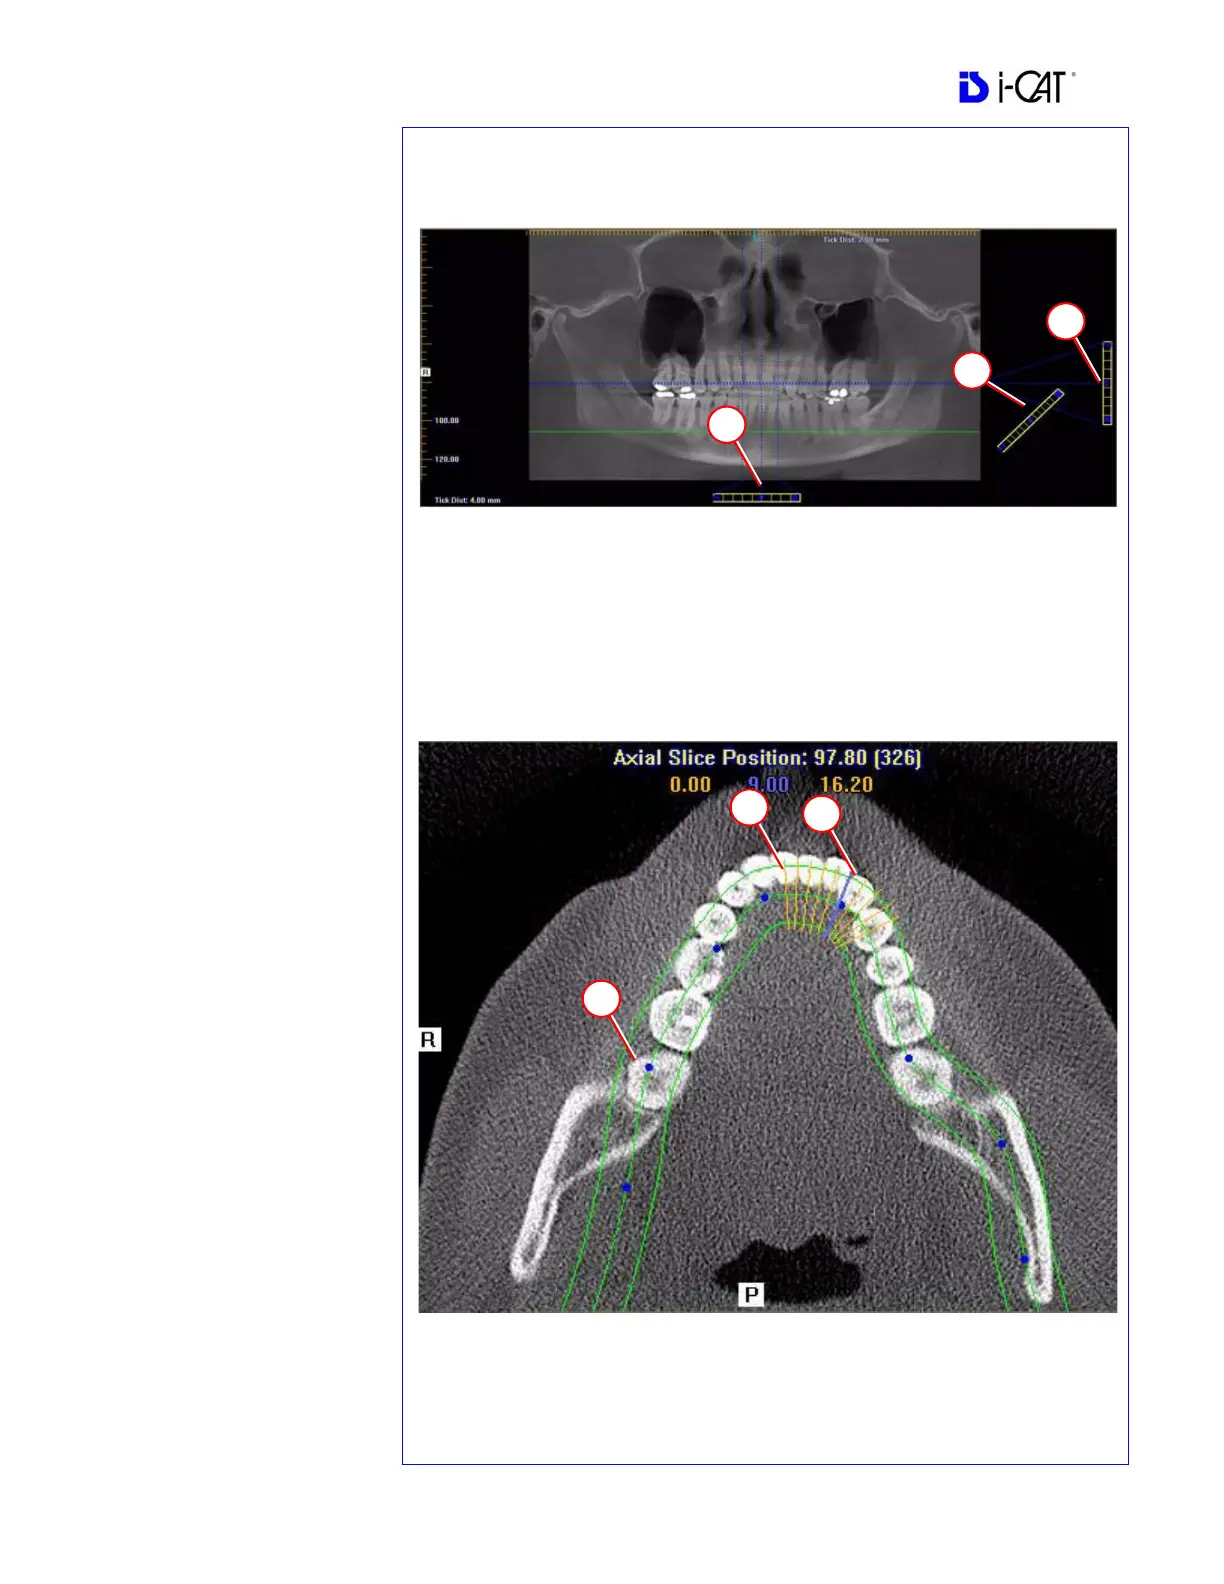

PAN TOOLS

1. Horizontal Tool Bar

Drag the center control button

of tool left to right to move the

slice location of the Cross

Sections. The center slice is

outlined in Blue on the Cross

Sections.

Drag the right control button of

tool to the right to adjust the

slice thickness of the Cross

2. Diagonal Tool Bar

Drag the top control button of

the tool to adjust slice thickness

of Panoramic View.

of the tool to adjust Pan Focal

Trough. Not functional with the

Tru-Pan feature.

3. Vertical Tool Bar

Drag the control button of the

center tool up or down to adjust

height of anatomy viewed in the

Cross Sections and Axial.

AXIAL TOOLS

1. Drag blue dots to adjust Pan

Map.

2. Orange hash marks are Slice

Location Indicators.

3. Blue hash mark represents the

centerline of the axial slices

displayed on the Cross Section

views.

Panoramic Map

Axial Slice Position